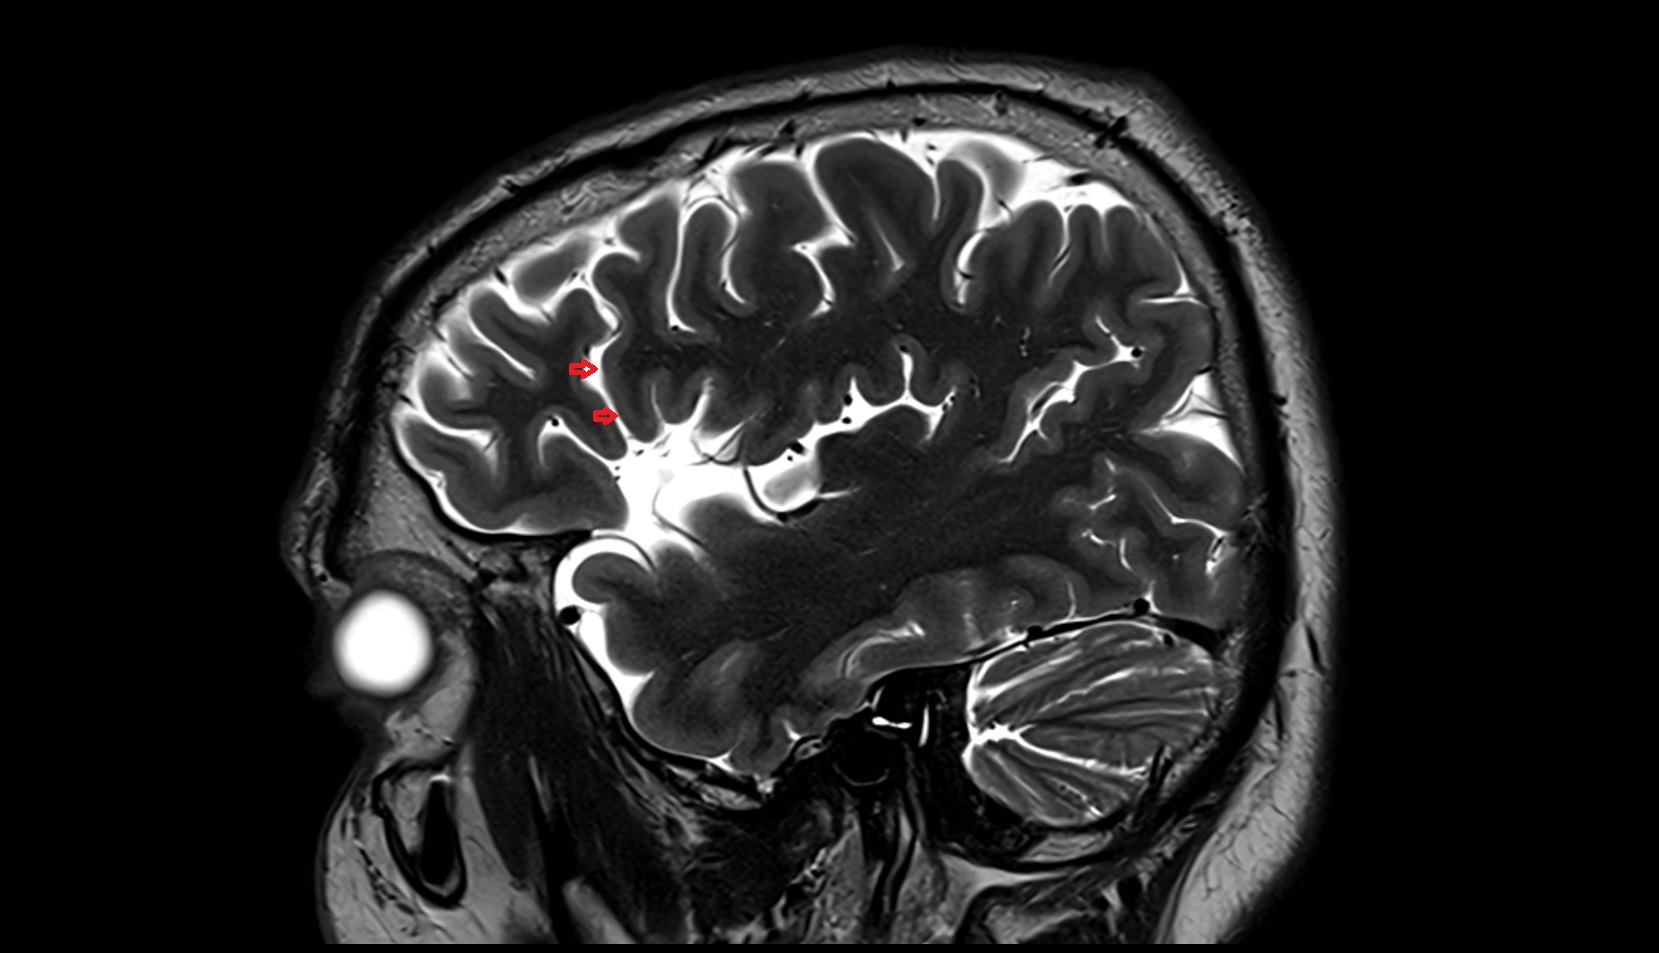

- Central sulcus